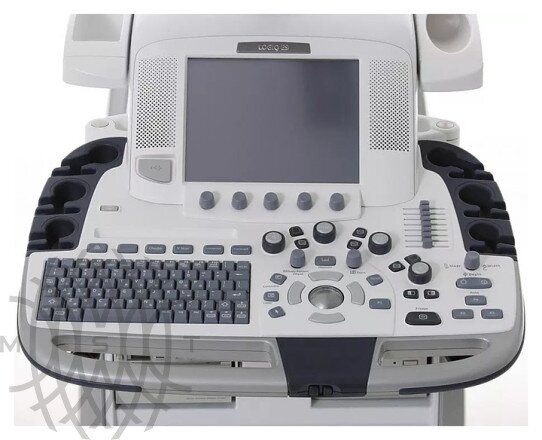

GE Logiq E9 XDclear аппарат УЗИ

- 22" жидкокристаллический монитор высокого разрешения на свободно регулируемом кронштейне.

- Эргономичный интерфейс пользователя с 10,4" цветной сенсорной панелью.

- 4 функционирующих бесштырьковых разъема для датчиков.

Высокая эргономика и оптимизированный рабочий процесс

Интуитивно понятный интерфейс пользователя, удобные элементы управления, регулируемая панель, а также многочисленные инструменты автоматизации делают процесс исследования более комфортным и быстрым.

- Ассистент сканирования — средство автоматизации всех этапов исследования, позволяющее существенно уменьшить число нажатий на клавиши и сократить общее время обследования.

- Ассистент измерений — инструмент для автоматического определения границ объектов, требующий от оператора всего несколькими нажатий на клавиши.

- Ассистент сравнения — позволяет сопоставить на разделенном экране дынные предыдущих исследований с текущим ультразвуковым изображением в режиме реального времени. Инструмент обеспечивает точное воспроизведение предыдущего исследования, сохраняя частоту, фокусы и прочие параметры.

- Работа с «сырыми» данными — технология позволяет получить доступ к исходным ультразвуковым данным ранее произведенного исследования для работы с ними без необходимости в присутствии пациента.

- Автоматические измерения и оптимизация изображения в различных режимах.